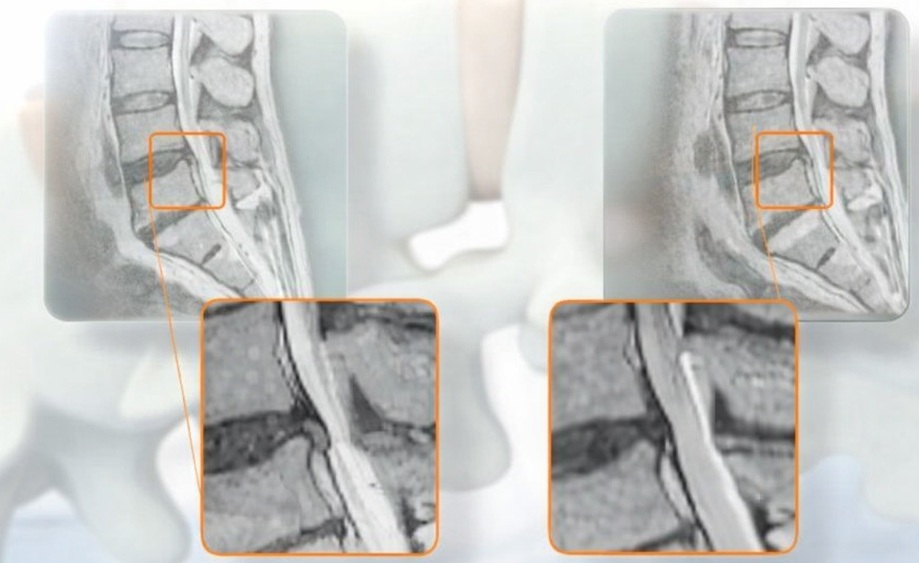

У повсякденному житті міжхребцеві диски стискаються під дією власної ваги тіла, фізичних навантажень. Це призводить не тільки до зменшення їх товщини, але й руйнування. Спочатку диск випʼячується (розвивається протрузія), а потім фіброзне кільце тріскається, і желеподібне пульпозне ядро виходить за його межі, утворюючи екструзію — міжхребцеву грижу. Вона може тиснути на спинний мозок, корінці спинномозкових нервів, викликаючи неврологічні порушення різного ступеню тяжкості та інвалідизацію.

Тракція — це дія, спрямована на розтягування хребта. При цьому простір між хребцями збільшується, і випʼячування міжхребцевих дисків втягуються у зворотному напрямку. Для забезпечення такої лікувальної дії, механотерапії, був винайдений тракційний стіл.